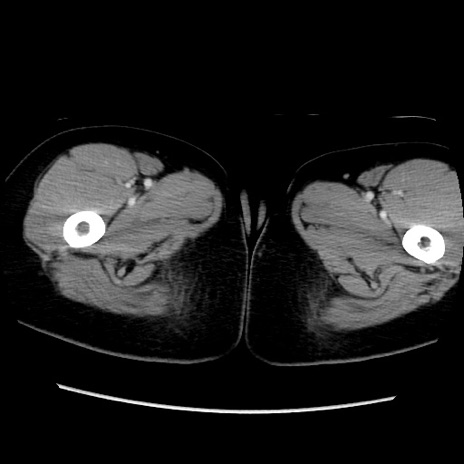

MRI(4日後)

【症例】40歳代女性

【主訴】上下腹部痛

【現病歴】2日目から下腹部痛あり。夜間は痛みで眠れなかった。昨日より上腹部痛と下痢が出現。臥位で痛みは軽快したため、休んでいた。本日になって臥位でも立位でも痛みが強くなってきたため救急要請。

【既往歴】子宮内膜症

【身体所見】部:平坦・軟、左上下腹部に圧痛あり、反跳痛あり。

【データ】WBC 21800、CRP 26.78